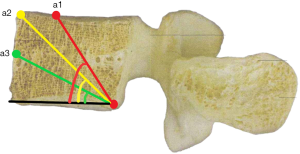

a1: the angle between the line, which is from the posterior-lower corner of the upper vertebral body to front-middle 1/3 of the upper endplate, and lower endplate parallel line.

a2: the angle between the line, which is from the posterior-lower corner of the upper vertebral body to anterior-upper corner, and lower endplate parallel line.

a3: the angle between the line, which is from the posterior-lower corner of the upper vertebral body to the midpoint of the anterior border, and lower endplate parallel line.

b1: the angle between the line, which is from the posterior-upper corner of the lower vertebral body to front-middle 1/3 of the lower endplate, and upper endplate parallel line.

b2: the angle between the line, which is from the posterior-upper corner of the lower vertebral body to anterior-lower corner, and upper endplate parallel line.

b3: the angle between the line, which is from the posterior-upper corner of the lower vertebral body to the midpoint of the anterior border, and upper endplate parallel line.

c1: the angle between the projection, which is generated from the posterior corner of the upper vertebral body to contralateral front-middle 1/3 on the endplate, and the tangent line to the posterior border of the vertebral body.

c2: the angle between the projection, which is generated from the posterior corner of the upper vertebral body to contralateral anterior corner on the endplate, and the tangent line to the posterior border of the vertebral body.

c3: the angle between the projection, which is generated from the posterior corner of the upper vertebral body to the midpoint of the anterior border on the endplate, and the tangent line to the posterior border of the vertebral body.

The included angles a1, a2, a3, b1, b2, b3 and c1, c2 and c3 in the sagittal plane were significantly different (P≤0.001) (Figure 13) (a1 > a2 > a3, b1 > b2 > b3, c1 < c2 < c3). In the angles of sagittal down-path, b1, b2 and b3 change significantly and consistently, showing a trend of decreasing first and then increasing, which is the smallest at L3 (46.08±4.37°, 36.21±3.51°, 22.47±3.01°) and the largest at S1 (69.49±8.28°, 61.23±7.74°, 36.60±5.00°). In the angles of sagittal up-path, a1 and a2 change in the same way, showing an increasing trend. While a3 goes down and then goes up, which is the smallest at L4 (23.43±4.29°) and the largest at L5 (24.36±2.94°). In the angles of axial plane, c1, c2 and c3 change in the same way, showing a trend of increasing first and then decreasing. c1 and c2 are the largest at L2 (40.07±2.75°, 55.1±3.32°), and c3 is the largest at L3 (73.11±2.10°). c1, c2 and c3 are the smallest at S1 (33.87±2.94°, 47.92±3.54°, 67.15±3.60°) (Figures 14,15).